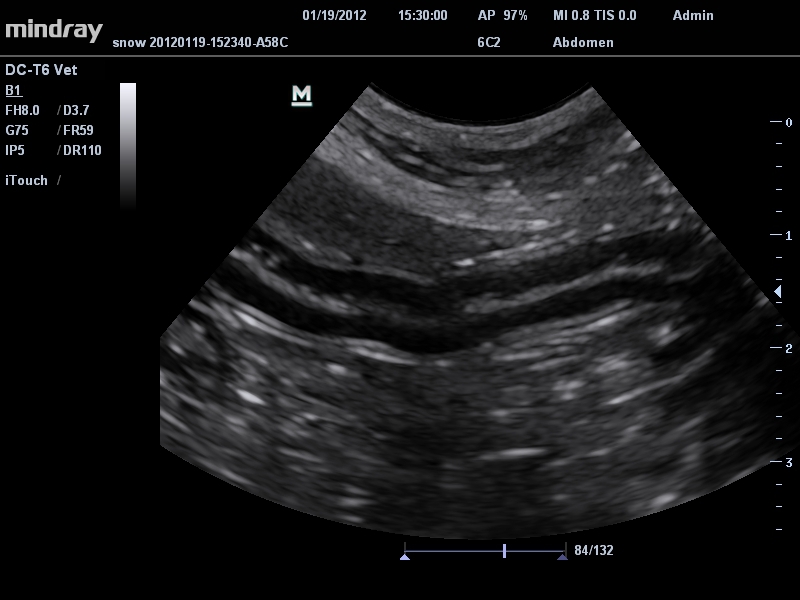

Ветеринария:

Да

• Микроконвексный датчик Mindray 6C2